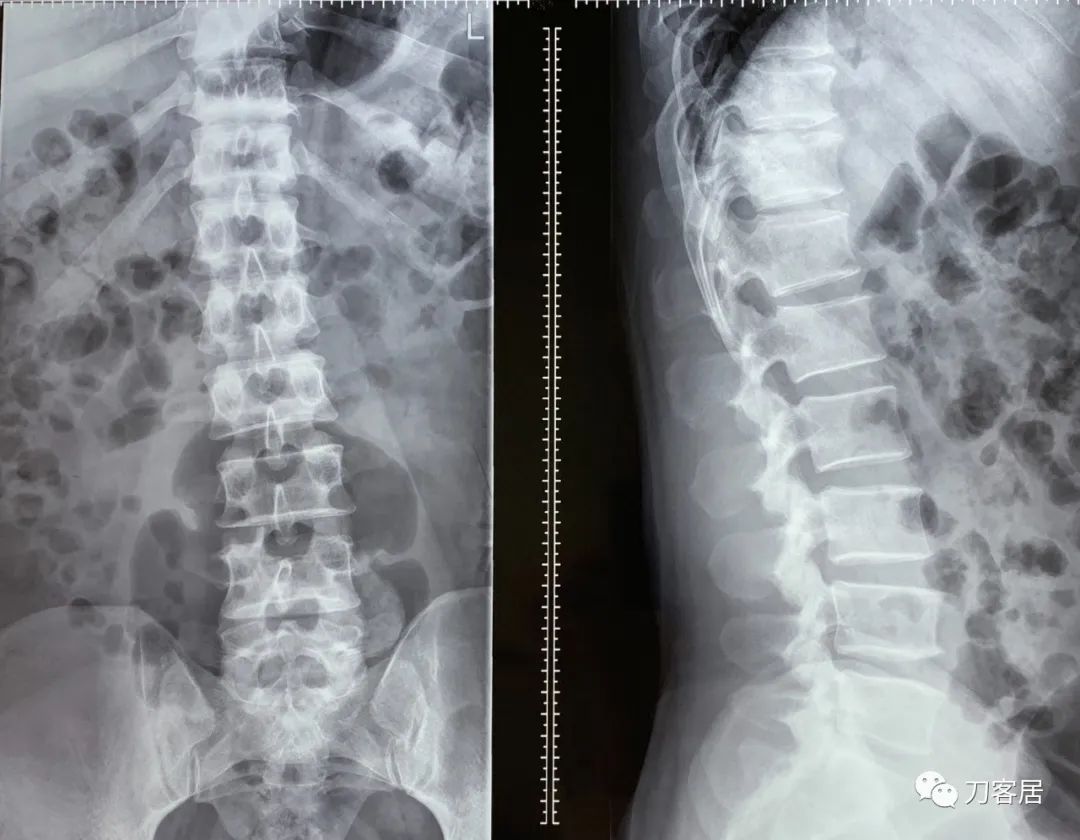

图1. 20220117宁夏医科大学总医院腰椎正侧位X线片

自带腰椎磁共振提示腰5骶1椎间盘突出,左旁侧型,腰3-5椎间盘突出,不严重。